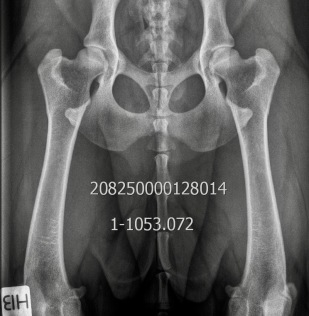

HD: A/A

AD: 0/0